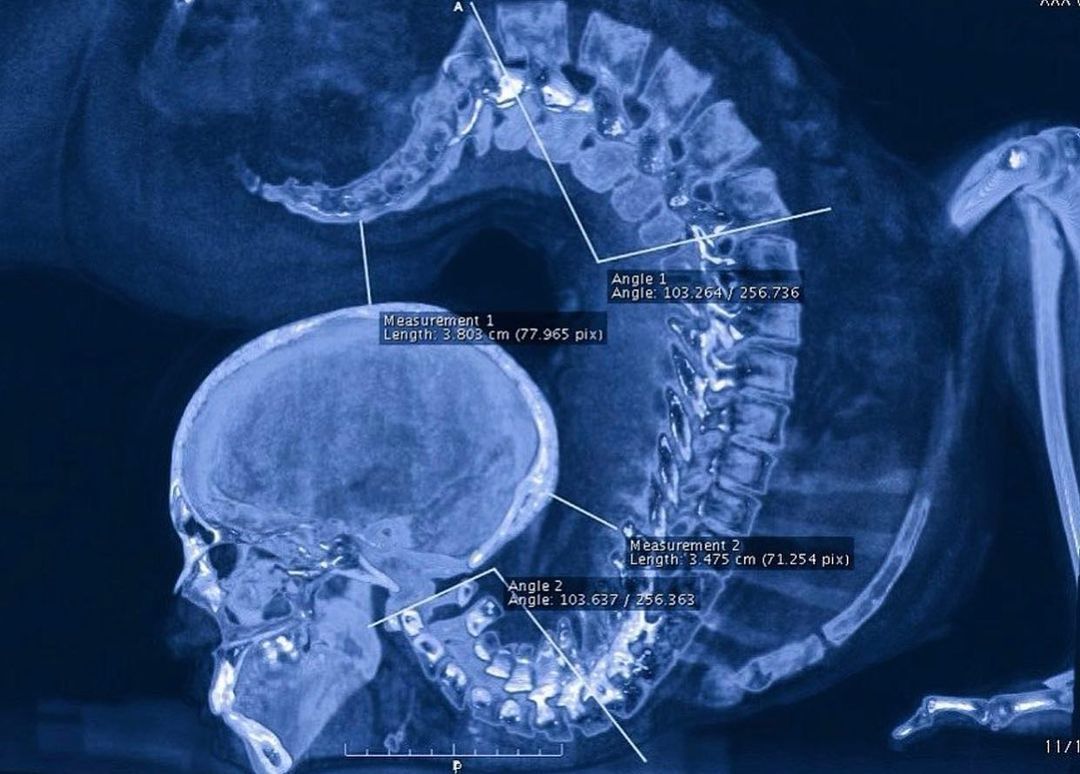

What you're looking at is an x-ray of an individual in an extreme pose of spinal extension! Contortionists excel at extreme physical flexibility. They twists and bends their body into strange and unnatural positions. Note how the thoracic spine stayed almost completely straight. Contortionists, gymnasts, dancers, yogis, all of these athletes excel at their sport with exceptional spinal flexibility. But at what cost? The spine forms the central axis of the skeleton, supports the skull, and gives attachment to the thoracic cage, pectoral girdle, and upper limb. It combines strength with great flexibility as it has many joints close together. Movements of the spine are possible due to intervertebral discs, and with the fulcrum of movement occurring primarily around the nucleus pulposus. Specialized motion occurs at the atlanto-occipital and atlantoaxial joints, which do not contain a disc. Flexion and extension are common to all parts of the spine; a significant degree of flexion/extension can be achieved at the atlanto-occipital joint, cervical and lumbar spine, but is restricted in the thoracic spine. Lateral flexion is free at the atlanto-occipital joint, cervical and lumbar spine, but less free in the thoracic spine. Rotation is greatest at the specialized atlantoaxial articulations, and to a lesser degree in the cervical and lumbar spine. A medical publication from 2008 suggests that long-term damage to the spine is common in long-term contortion practitioners. A study of five practitioners using magnetic resonance imaging (MRI) by Peoples et al, documented limbus vertebrae, intervertebral disc bulges, and disc degeneration. Three of the five practitioners also reported back pain.